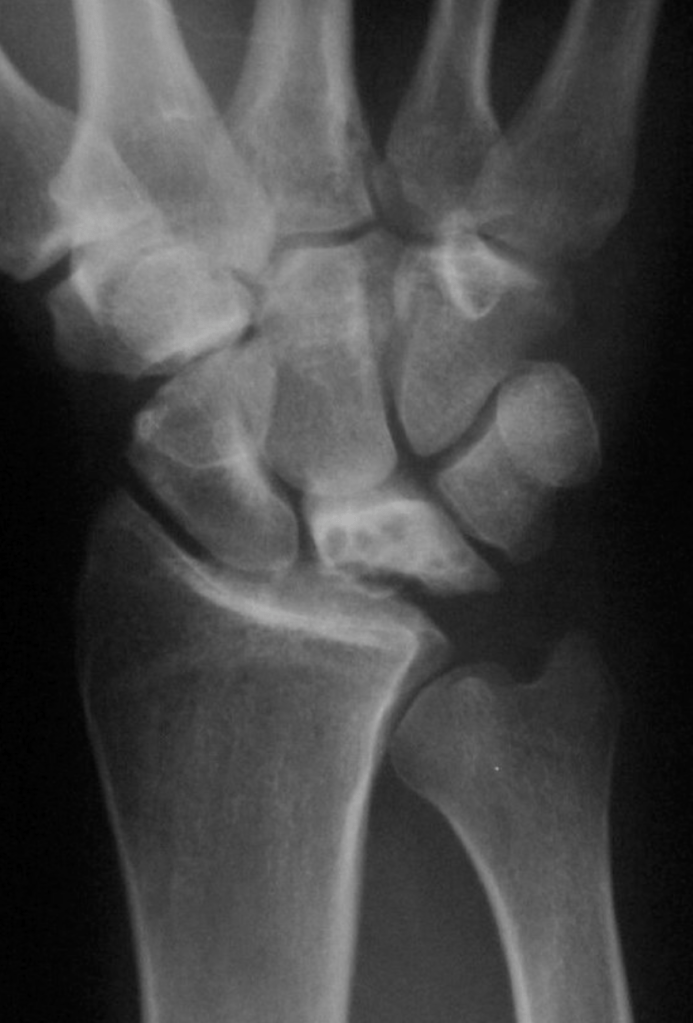

It is actually difficult to determine what will be the natural history of Kienbock’s disease in patients who first present. The condition is sometimes diagnosed very early on, before any X-ray changes are seen. In other patients the condition presents when the lunate bone fractures or breaks because of bone death.

Kienbock’s disease can be classified according to the changes seen on xrays and scans, and we try to classify the condition in all patients, so that we can give an idea of what is likely to happen. If, for example, a patient presents with stage 2 Kienbock’s, but 6 months later has progressed to stage 3, then we assume that the disease process is active. If no progression of the condition is seen on serial xrays, then we can say that the disease process is static.

At the other end of the spectrum, in some patients the bone seems to collapse and crumble, with the development of osteoarthritis and consequent loss of movement with increased pain.